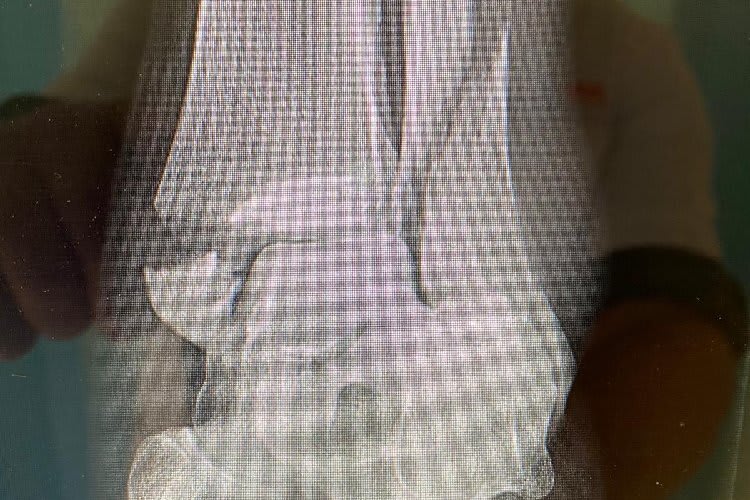

Durch eine unglückliche Situation vor einem Monat beim Motocross sein linker Fuß derart heftig verdreht, dass Schien- und Wadenbein unmittelbar oberhalb des Sprunggelenks brachen!

Eine Operation war unausweichlich, doch wegen der starken Schwellung musste der auf der Karibikinsel Curacao geborene Van Sikkelerus zwei Wochen warten. Mit zwölf Schrauben und viel Metall wurden die Brüche in einer schwierigen Operation Anfang Juli fixiert.

"Ich bin so sauer! Ausgerechnet jetzt, wenn die Saison wieder losgeht, passiert sowas", schimpfte Van Sikkelerus. Als mein Fuß den Boden berührte und sich verdrehte, wusste ich sofort, dass etwas schlimmes passiert ist. Es war eine schwierige Operation und es ist auch ziemlich schmerzhaft. Aber der Eingriff war erfolgreich. Mit zehn Schrauben wurde das Schienbein versorgt, mit zwei Schrauben das Wadenbein. Wir werden jetzt alles tun, um so schnell und so gut wie möglich fit zu werden."